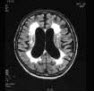

50、单项选择题

患者,女,70岁,有高血压和糖尿病史,左侧肢体活动不灵,突发外出迷路1天入院。MRI显示如图。

常见的病理改变不包括()

A.脑出血

B.脑梗死

C.脑萎缩

D.侧脑室扩张

E.血管平滑肌中层细胞嗜锇颗粒沉积